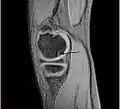

| A large flap lesion in the femur head typical of late stage Osteochondritis dissecans. In this case, the lesion was caused by avascular necrosis of the bone just under the cartilage. | |

Magnetic resonance imaging (MRI) is useful for staging OCD lesions, evaluating the integrity of the joint surface, and distinguishing normal variants of bone formation from OCD by showing bone and cartilage edema in the area of the irregularity. MRI provides information regarding features of the articular cartilage and bone under the cartilage, including edema, fractures, fluid interfaces, articular surface integrity, and fragment displacement.[37][38] A low T1 and high T2 signal at the fragment interface is seen in active lesions. This indicates an unstable lesion or recent microfractures.[30] While MRI and arthroscopy have a close correlation, X-ray films tend to be less inductive of similar MRI results.[38]

Sagittal MRI: Linear low T1 signal at the articular surfaces of the lateral aspects of the medial condyle of the femur confirms the presence of OCD.